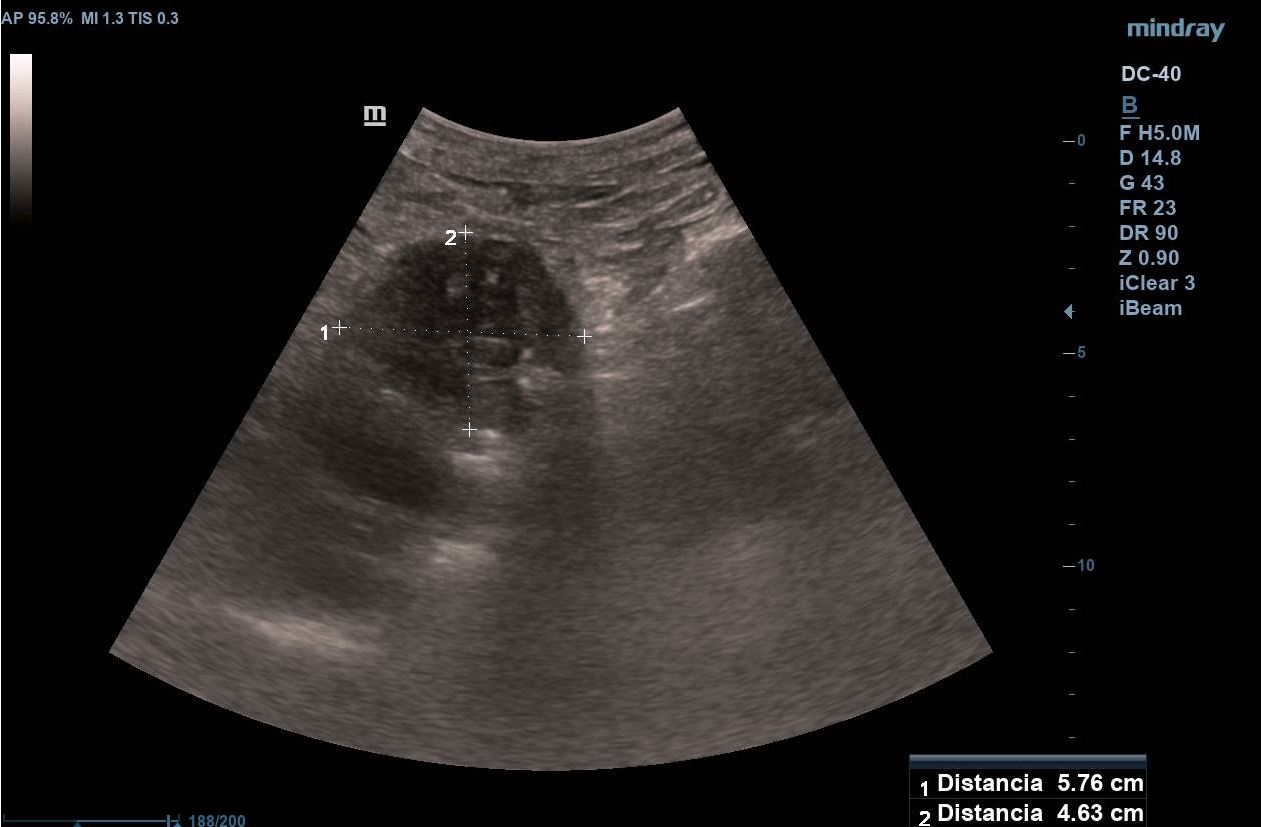

Se realiza ecografía clínica abdominal visualizando en región epigástrica masa de 5,7 x 4,6 cm de aspecto heterogéneo, con un componente principal hipoecogénico y áreas de mayor intensidad. Presenta mapa color positivo y dilatación de colédoco.

Se inicia estudio, confirmando en ecografía abdominal reglada la presencia de una masa sólida en cabeza-cuello pancreático de 5 x 4 cm con dilatación de la vía biliar intra y extrahepática y en TAC toraco-abdomino-pélvico masa hipervascular en cabeza y cuerpo pancreático con áreas de degeneración quística, dilatación del árbol biliar y atrofia del páncreas distal. Posteriormente, se realiza una ecoendoscopia en la que se informa de una masa pancreática con engrosamiento de la papila duodenal, así como dilatación de la vía biliar extrahepática.